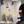

附四维图两张!